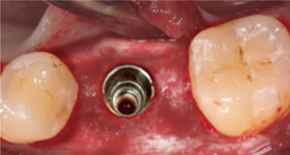

1. Before surgery

2. No incision, Minimal implant hole

3. Placing MagiCore